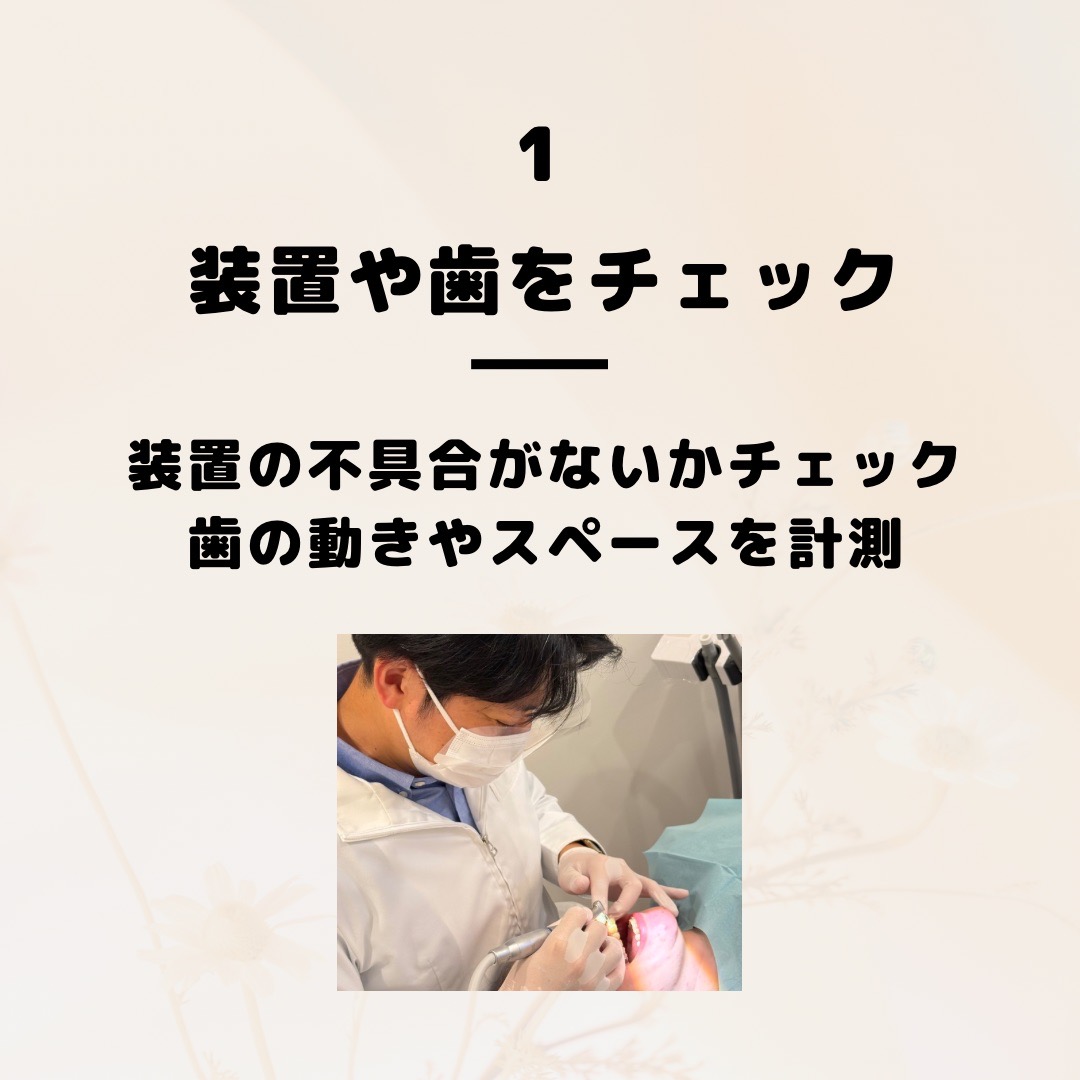

④動的処置(矯正装置による歯の移動)

月に1回程度の通院で、歯の動きを確認しながら適切に調整を行います。